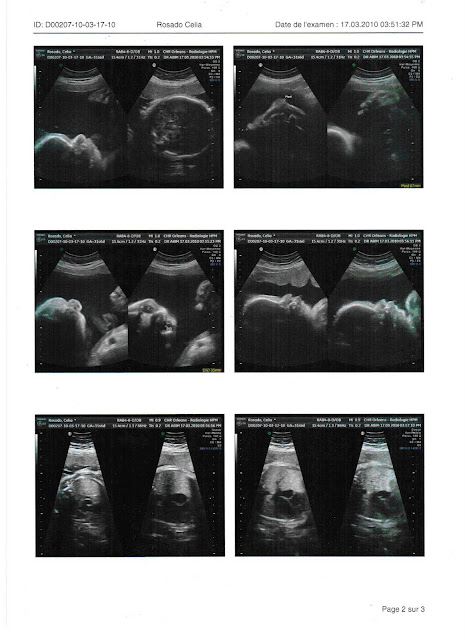

O casulo do F aos sete meses.

A primeira imagem da ecografia são os testículos ( a médica disse que também lá está a pila! lol). Depois a coluna, a última da primeira página é a cabeça. As duas seguintes são a cabeça e o cérebro, depois as narinas - 3ªfoto da 2ª pág - (vêem-se bem os dois buraquinhos...), ao lado são os olhos, as outras 3 fotos da 2ª pág já não sei o que são... a 2ª foto da 3ª pág é a barriga, nas duas seguintes são as costelas e os rins - agora é mais difícil de perceber os orgãos porque os ossos já estão calcificados. As 2 últimas são da placenta, vista de cima e de baixo e numa delas dá para ver uma orelhita.

Ah e o peso estimado do rapazote é de 1,980 kg, ora fazendo as contas por alto, a uma média de mais 200 gr por semana e sabemos que faltam cerca de 8 semanas, vai ser moço para ter perto de 3,5 kg à nascença... bom, mas bom!!!